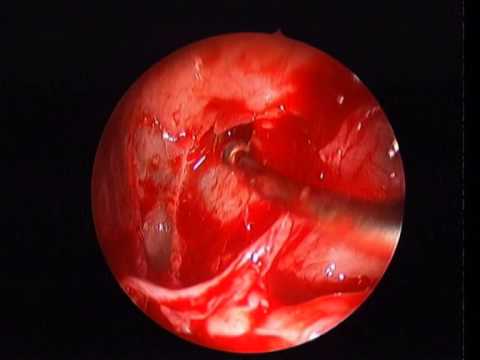

FRONTAL TREPHINEING FOR DIFFICULT FRONTAL RECESS EXPLORATION WHICH IS SAFE,SURE,SECURE AND SIMPLE